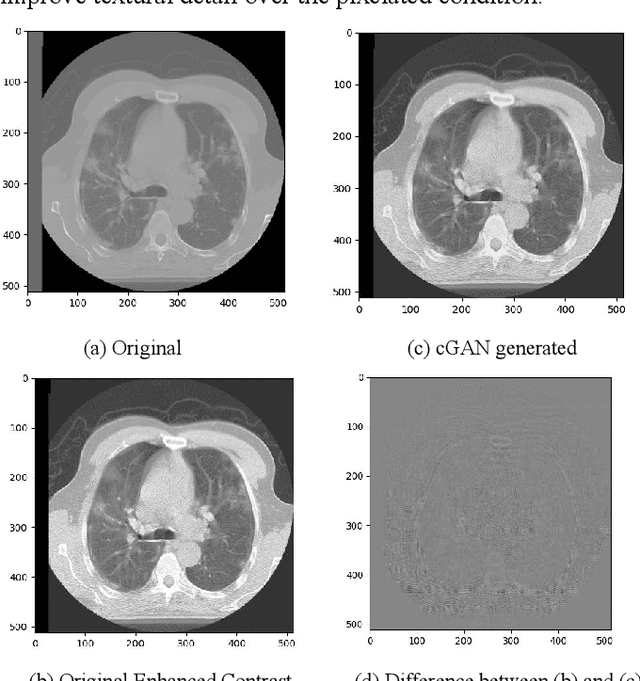

Abstract:We present a novel conditional Generative Adversarial Network (cGAN) architecture that is capable of generating 3D Computed Tomography scans in voxels from noisy and/or pixelated approximations and with the potential to generate full synthetic 3D scan volumes. We believe conditional cGAN to be a tractable approach to generate 3D CT volumes, even though the problem of generating full resolution deep fakes is presently impractical due to GPU memory limitations. We present results for autoencoder, denoising, and depixelating tasks which are trained and tested on two novel COVID19 CT datasets. Our evaluation metrics, Peak Signal to Noise ratio (PSNR) range from 12.53 - 46.46 dB, and the Structural Similarity index ( SSIM) range from 0.89 to 1.